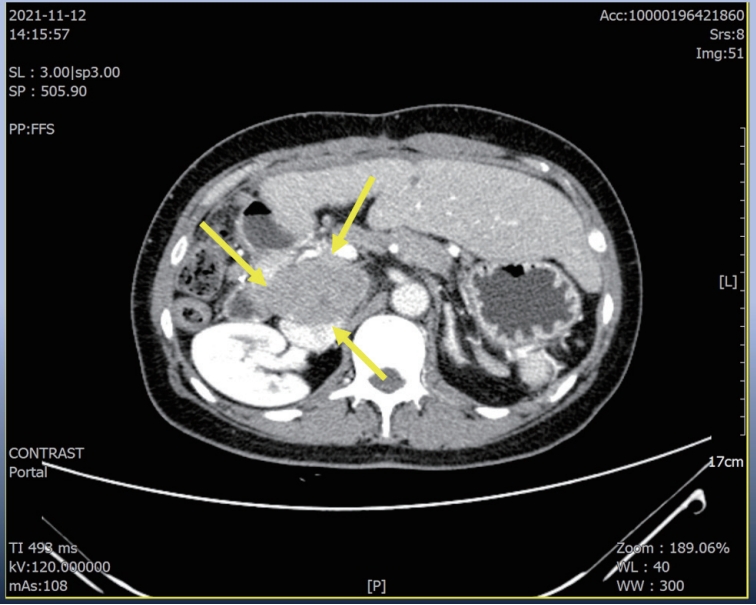

Figure 2.Liver CT scan (A–C) and chest CT scan (D) after seven cycles of 1st line Ate+Beva therapy. Almost peritoneal metastasis were shrinked (A). However prerenal (B) and peripancreatic (C) lymph node metastasis were increased and new onset lung metastasis was detected (D). CT, computed tomography; Ate+Beva, atezolizumab plus bevacizumab.

® 15 mg/kg per dose; Genentech, South San Francisco, CA, USA) were administered every 3 weeks on the same day. Following the seven cycles of Ate+Beva, liver CT scan revealed several peritoneal and LN metastasis were decreased compared to the prior CT scan (

Fig. 2A). However prerenal and peripancreatic LN metastasis were increased, moreover new onset lung metastasis was happened (

Fig. 2B–

D). We concluded this mixed response as an oligo-progression and treated the patient with same systemic therapy (Ate+Beva) combining radiotherapy (RT) for prerenal LN metastasis (45 Gray/25 fraction). In follow-up CT scan that was conducted 6 months after commencing Ate+Beva plus RT, abdominal increasing LN metastasis previously was markedly shrinked (